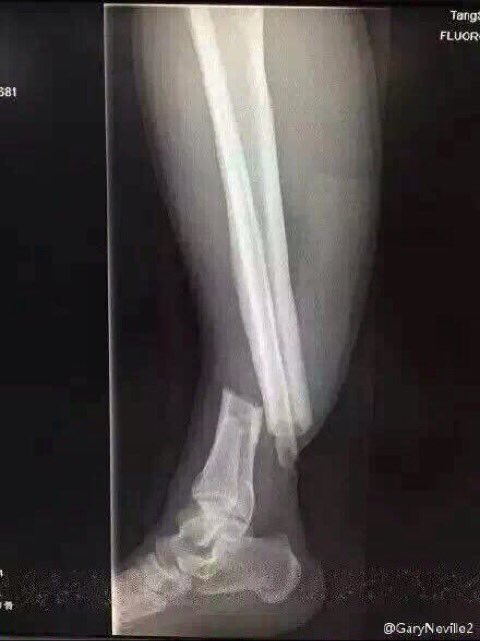

広州恒大のdfゾウ ジェンの足首の怪我は脱臼骨折か ノマドスタイル

FIFAクラブW杯準決勝\r 広州恒大のDFゾウジェン 左足に大ケガ ありえない方向に曲がる\r \r FIFAクラブW杯準決勝 広州恒大対バルセロナ\r 広州恒大(中国)のDFゾウ・ジェン(スーセイ)の\r 左脚があらぬ方向に曲がってしまった。\r 前半33分、ゴール前でバルセロナDFアウベスと競った際に負傷。 1990年生まれで年現在29歳のウー・ジンイェン。 「瓔珞」で脚光を浴び、NHKBSプレミアムで5月から放送開始の「コウラン伝」でも主演を張っています。 165センチ、44キロとスレンダーな体型。 時代劇の衣装では体型が全くわかりませんが、中国の女優 我らが創造営21のメンター、ナンナンこと「周震南(ゾウ・ジェンナン)」 17年に放送されていた「 明日之子 」という 音楽のオーディション番組で共演したメンバーです。